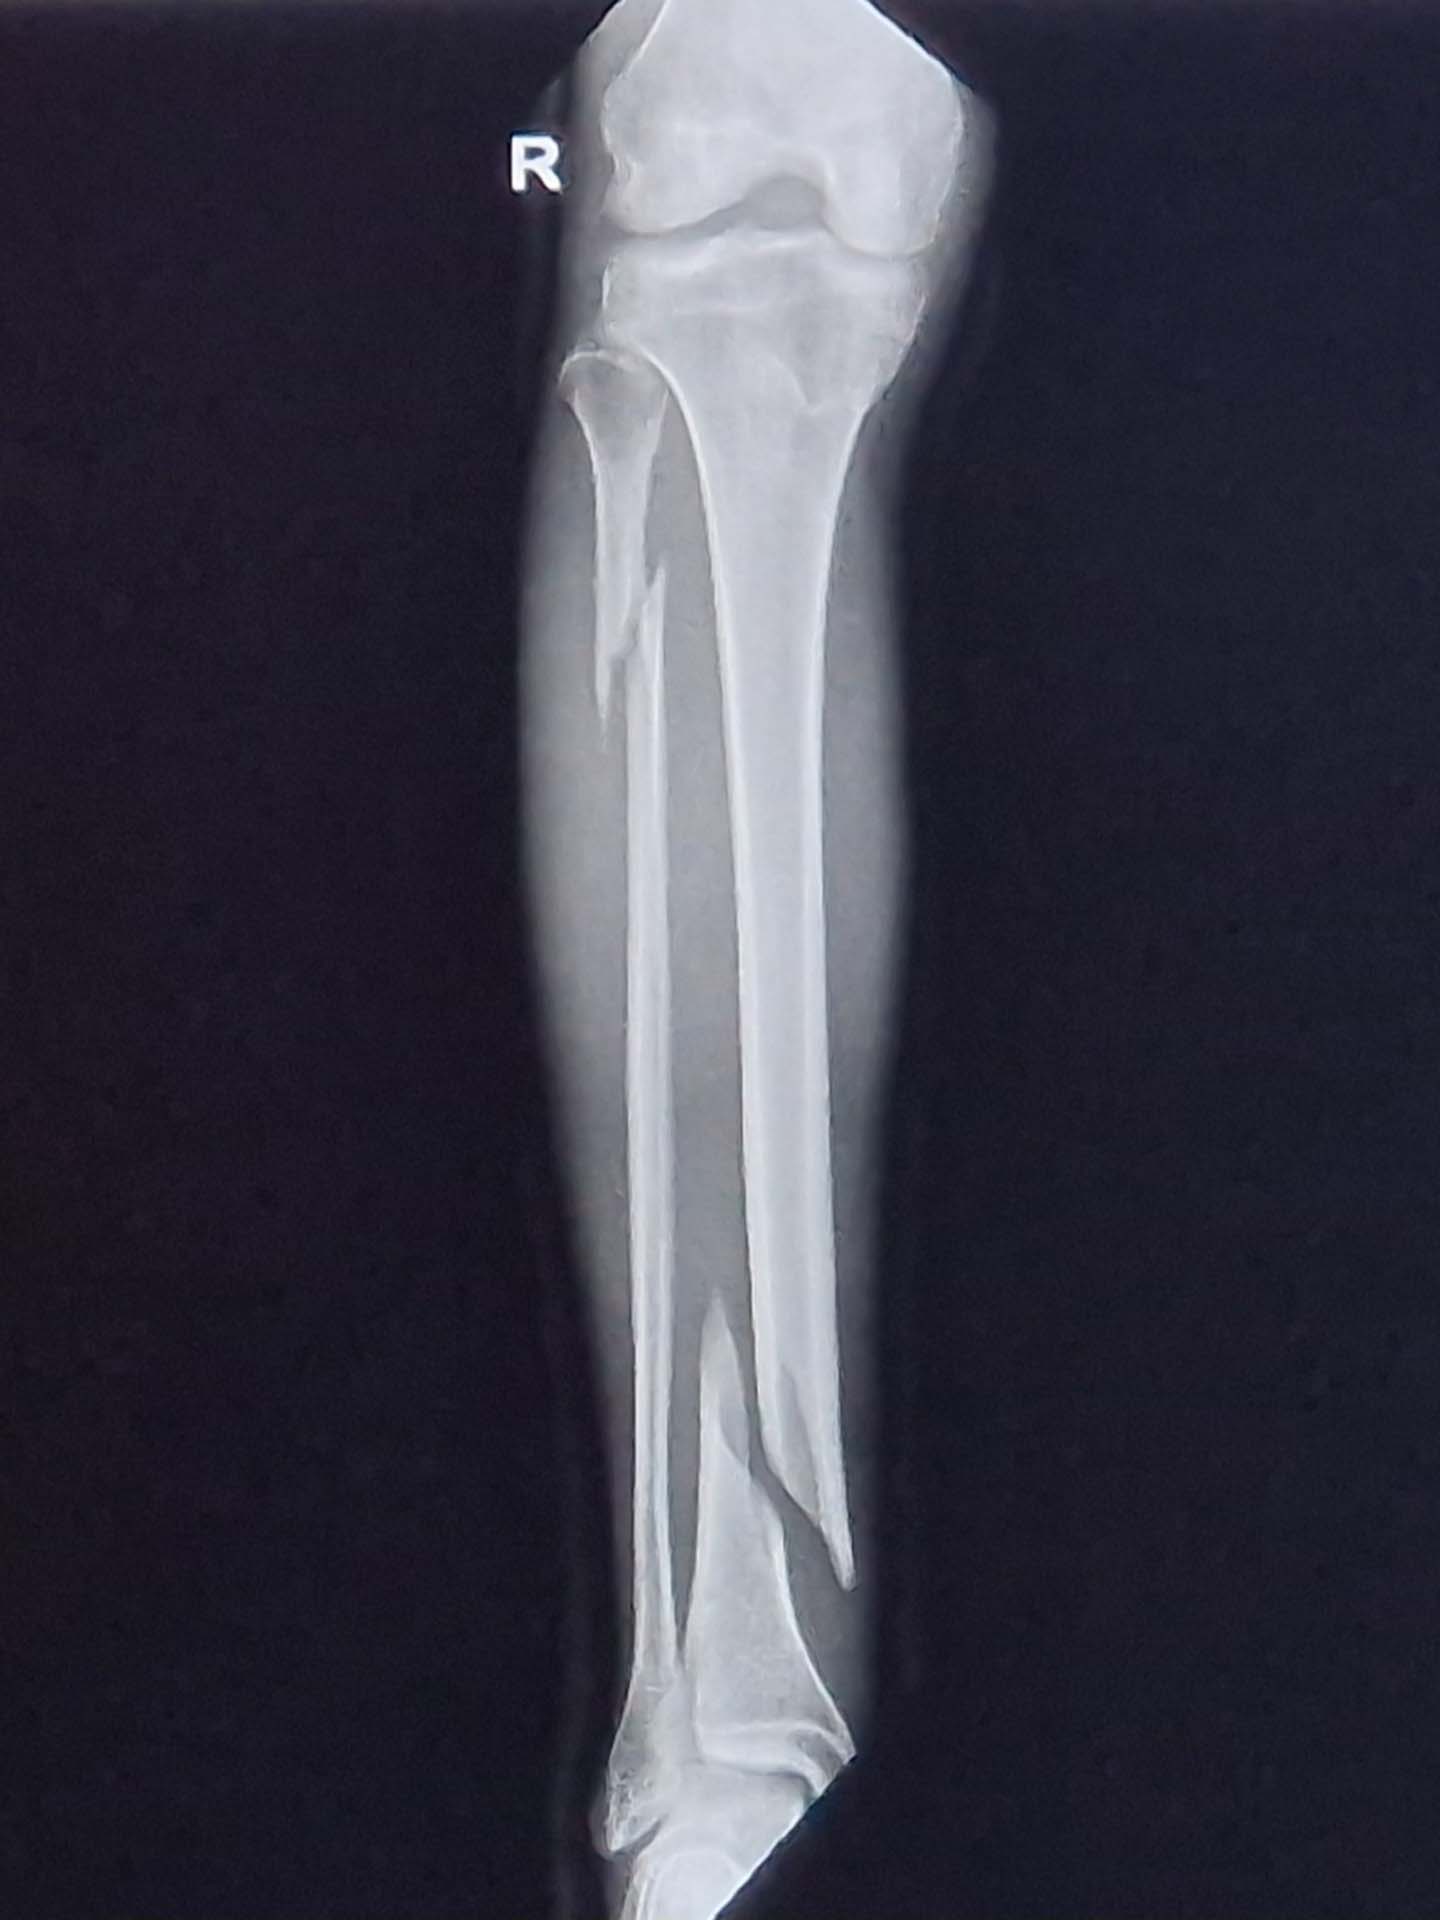

De dag van de operatie zelf kropen de minuten voorbij, vooral het uurtje dat ik aan de beurt zou zijn en maar niet werd opgehaald. Maar dan gaat alles ineens heel snel en als je wakker wordt ziet je binnenkant er ineens wat anders uit.